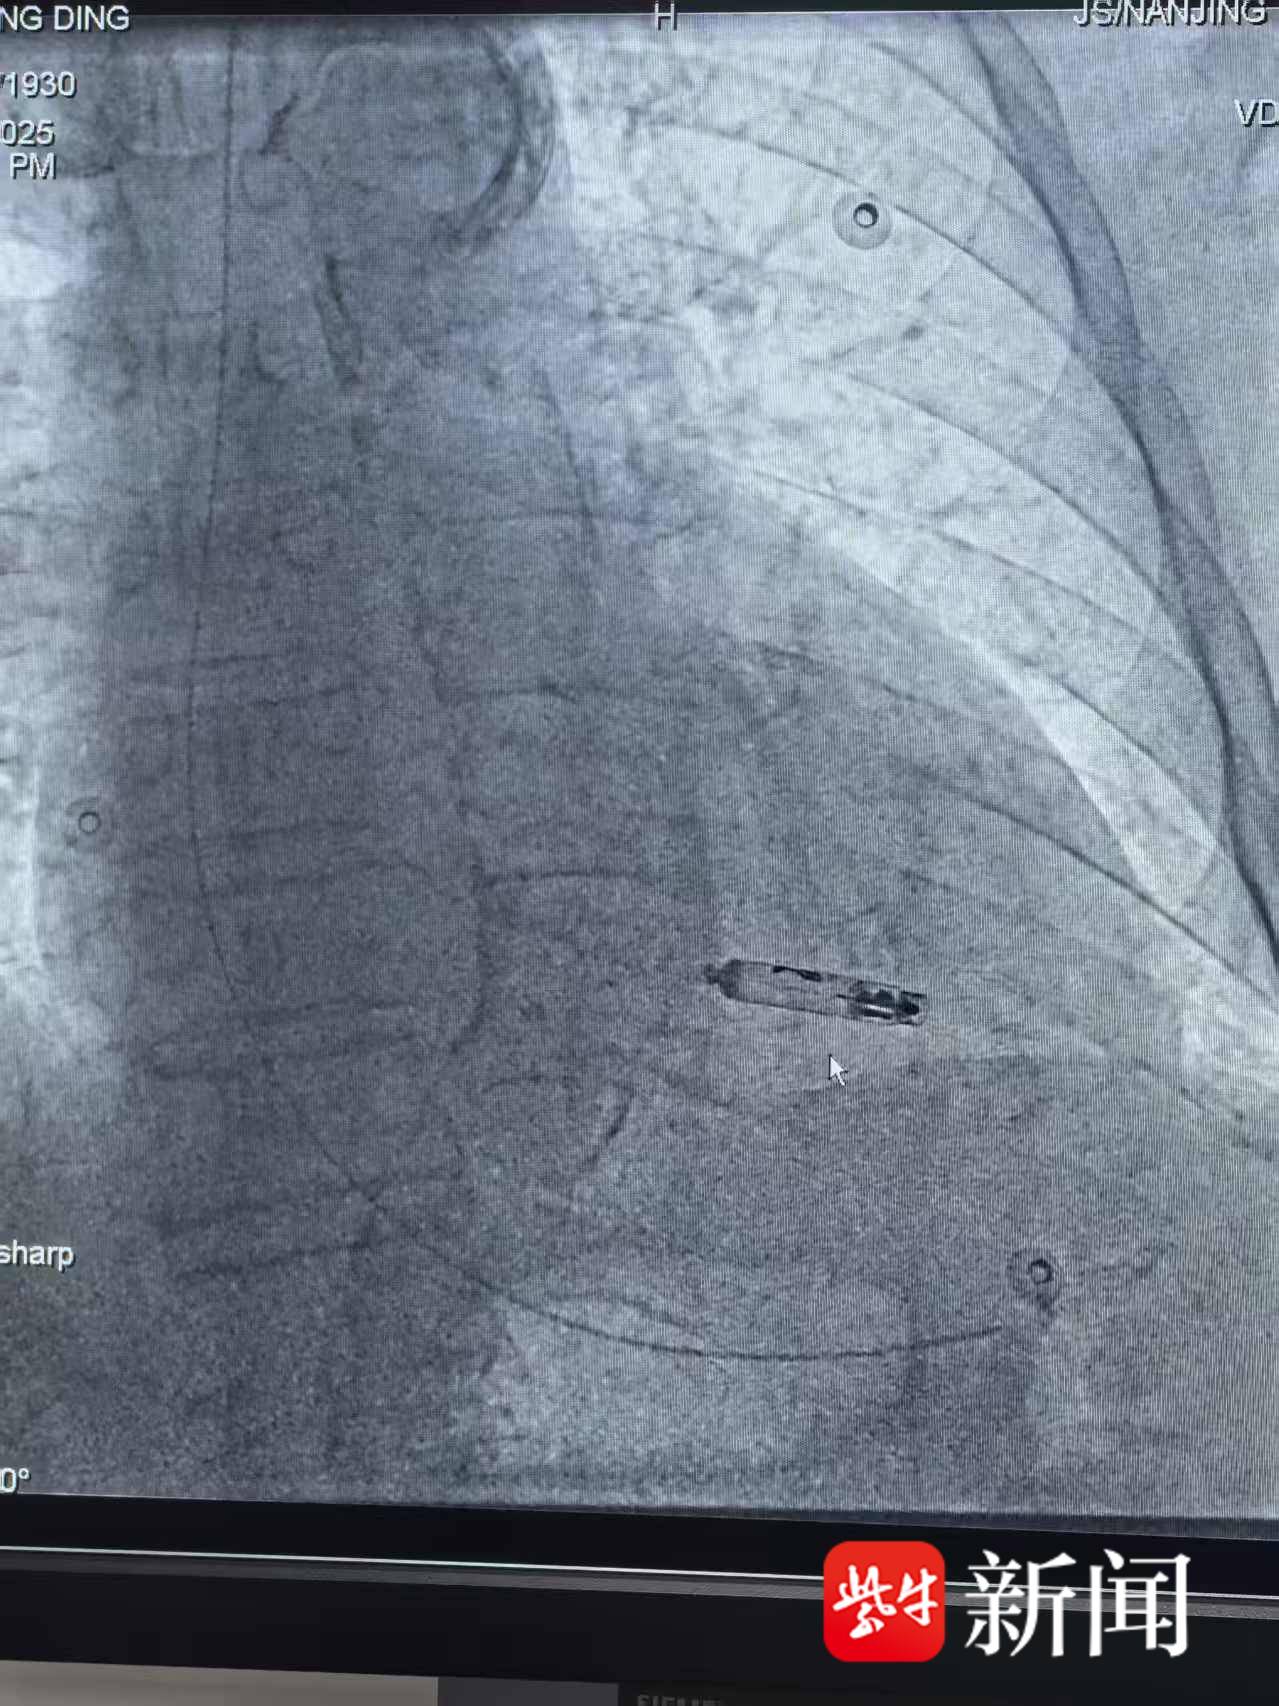

手术台上,汤涌主任通过患者大腿股静脉,将仅2克重的微型起搏器精准送至心脏最佳位置。在X线实时引导下,这个“胶囊”被稳稳固定在心室内壁。整个过程无开胸、无切口,仅耗时30分钟。